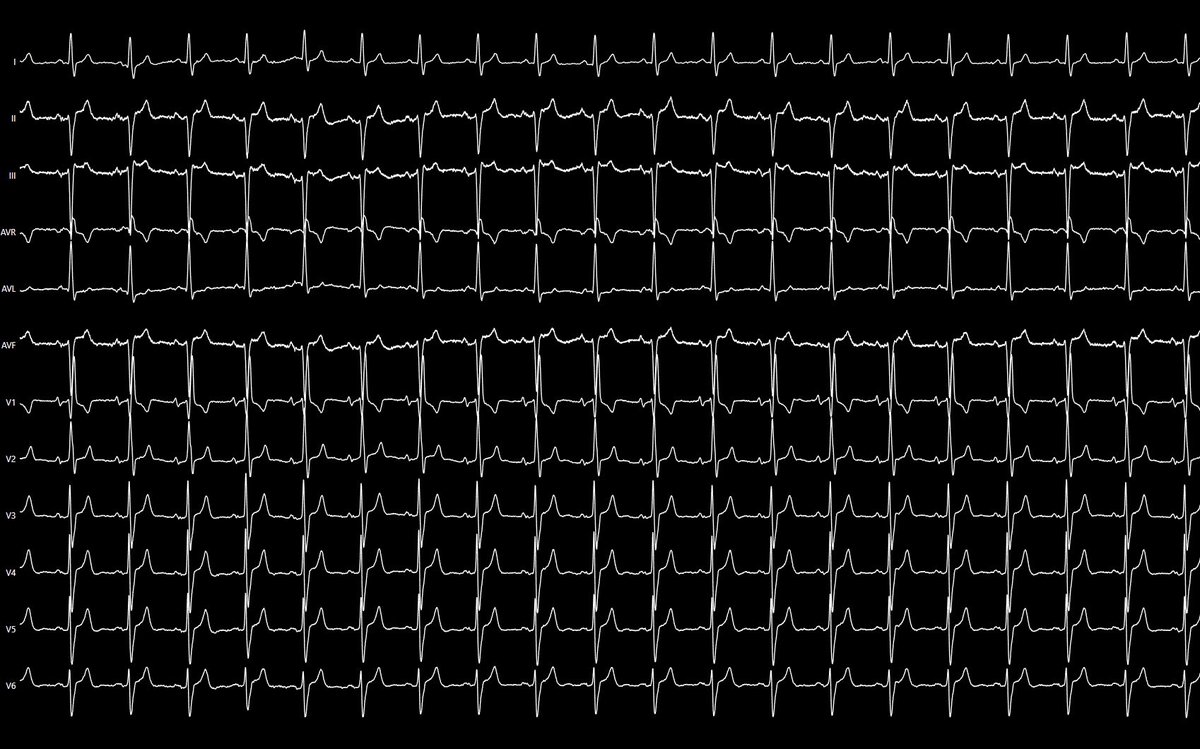

✅ Final EKG 👇🏼

@DrBerruezo @Davidsotoiglesi @daniviverosf #EPeeps #AblatePVC

Today’s case: LCC PVC ablation in a female patient with PVC-induced cardiomyopathy (PVC burden 35%).

📌 Total procedure time: 29 min.

📌 Fluoroscopy time: 80 sec.

📌 Single shot RF application (35W)

@DrBerruezo @BiosenseWebster #epeeps #ablatePVC #Carto